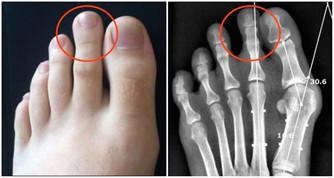

·腿部或腳部腫脹;

·背部疼痛,位置在腰部以上(腎臟位置);

·肌肉痙攣;

·血液循環不良;